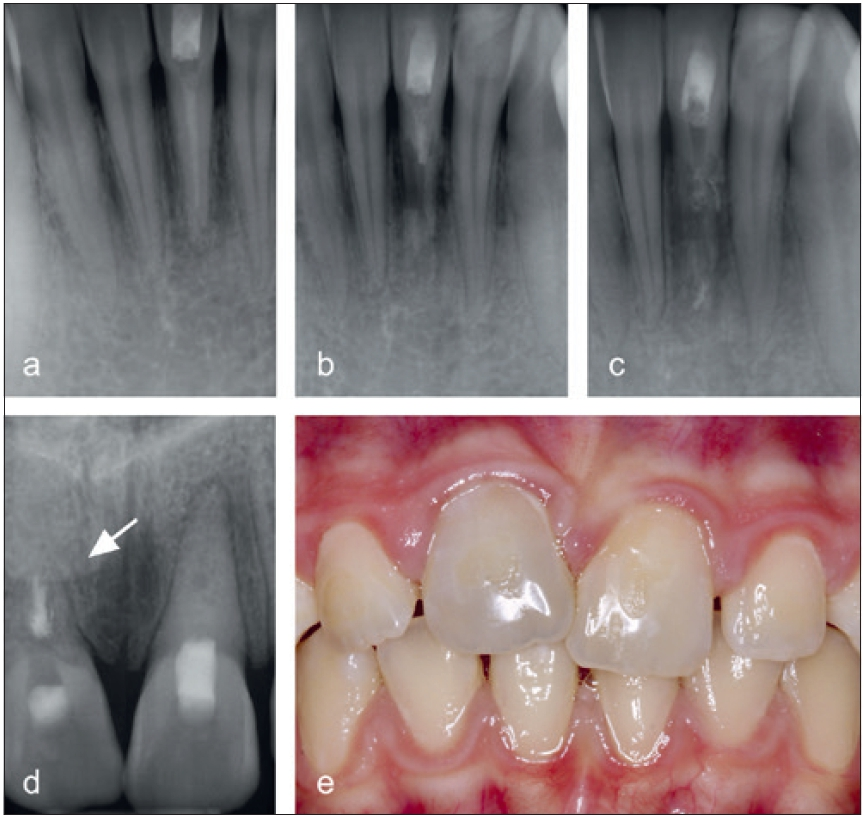

Sie verläuft häufig symptomfrei und wird oft im Rahmen von Routineuntersuchungen entdeckt. Es sind in der Regel tastbare zervikale Defekte vorzufinden, die mit Granulationsgewebe gefüllt sind, welches bei Berührung stark blutet (Abb. 7a bis c). Eine zunehmende Ausbreitung des hyperplastischen Resorptionsgewebes verursacht großräumige Defekte, die sich als rötliche Verfärbungen der Zahnkrone, sogenannte Pink-Spot-Läsionen, zeigen können (Abb. 7d). Radiologisch stellt sich die invasive zervikale Resorption meist als wolkige Aufhellung im Bereich des Zahnhalses dar (Abb. 7e und f). Ein typisches Merkmal ist auch das unversehrte perikanaläre Dentin, was als „Pericanalar Resorption Resistant Sheet“ (PRRS) bezeichnet wird [25,26]. Wie bereits erwähnt, ist Prädentin äußerst widerstandsfähig gegen resorptive Prozesse und stellt sich bis zuletzt als intakte Dentinbarriere dar (Abb. 8). Die invasive zervikale Resorption verläuft in mehreren Stadien [27]. Über einen Zementdefekt (Abb. 8) dringt das entzündliche Gewebe zunächst in die Zahnwurzel ein (Initiation). Bei weiteren bakteriellen Reizen, persistierenden Krafteinwirkungen oder Gewebehypoxie breitet sich die Resorption im Zahn in alle Richtungen aus (Progression). Im Laufe der invasiven Auflösung durch das entzündliche Gewebe kommt es zu einem knochenähnlichen Remodeling von Zahnhartgewebe (Reparatur).

Während invasive zervikale Resorptionen in der Progressionsphase radioluzente Läsionen zeigen, stellen sich die Defekte in der anschließenden reparativen Phase radioopak dar.